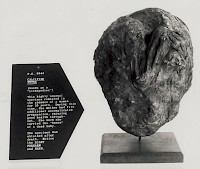

Der erste Fall eines Steinkindes wurde bereits im Jahre 1582 beschrieben und wurde als Steinkind von Sens beschrieben.

Eine Frau aus Sens (Burgund) zeigte 1554 im Alter von 40 Jahren alle Anzeichen einer normalen Schwangerschaft, doch das Kind wurde nicht geboren. Die Mutter hatte noch jahrelang Beschwerden und das ungeborene Kind war als harte Schwellung in ihrem Leib zu spüren. 28 Jahre später - nach ihrem Tod - ließ der Witwer sie sezieren. Im Leib der Mutter wurde ein großes eiartiges Gebilde gefunden, das nur mit Gewalt aufgebrochen werden konnte. Darin befand sich ein voll ausgetragenes, versteinertes Mädchen.